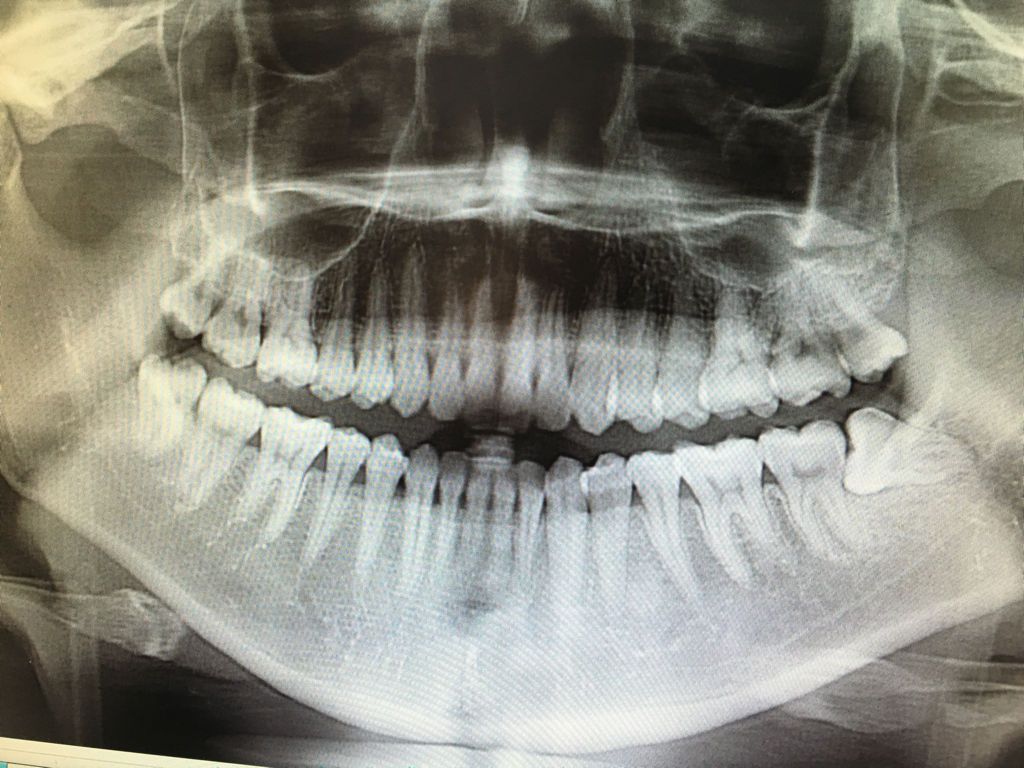

最近牙齿发炎,去拍片了!医生说建议我孕前拔掉4颗大牙!请专业医生帮我看看,我这样的需要拔牙吗?只有左下角的垂直阻生齿疼过,其它牙齿未曾疼过!

左下一定要拔,左上因为没有咬合了一般也建议拔,右边没有其他情况相命咬合良好可以保留。 非逝锅专业随口一说,靠谱的还是问问大夫为什么要拔,舞玻笼觉得有理就听,没理就不听

左下的应该拔掉,所以左上也没有用,应该一起拔掉。右边的如果不发炎,都能正常萌出,可以考虑不拔